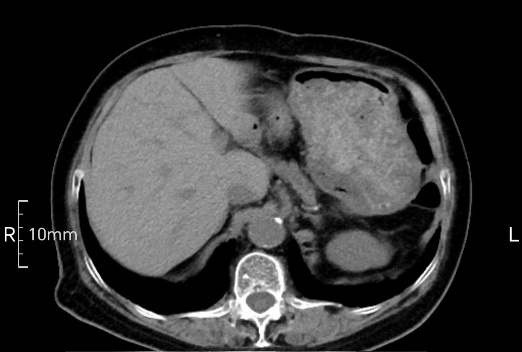

看看下面三幅便知遵醫囑的重要性。

完美禁食且喝飽飽,胃壁完美展現。